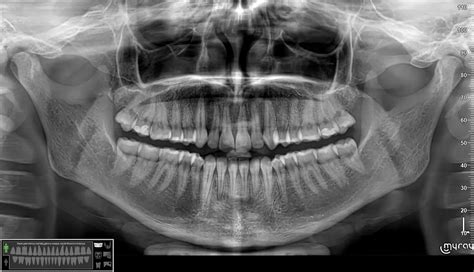

Ką galima pamatyti rentgeno nuotraukoje?

Susipažinkime su tuo, ką gali ir ko negali parodyti rentgeno nuotrauka.

- Šešėliai ten, kur jų būti neturėtų: Auglys arba infekuotas skystis esant pneumonijai plaučių srityje matomi aiškiai, kadangi piktybiniai audiniai ir skysčiai kur kas tankesni nei patys plaučiai, ir nuotraukoje ryškiai matomos tamsios dėmės. Auglys širdies arba skrandžio srityje greičiausiai bus ne taip ryškiai matomas arba netgi nematomas, kadangi tankumu širdies, skrandžio ir auglio audiniai kone nesiskiria.

- Perlūžę šešėliai ten, kur turėtų būti tiesūs: Sulaužytas šonkaulis paprastai matomas visiškai aiškiai, ypač jei lūžio galai šiek tiek persiskyrę, tačiau nedidelis įskilimas gali būti nematomas. Apskritai rentgenas nepatikimas identifikuojant bet kokius mažesnius nei dvylikos milimetrų diametro objektus

- Nenormaliai dideli arba maži šešėliai: Rentgenas sugeba išryškinti pernelyg padidėjusią širdį. Infarktas nepakeičia širdies dydžio arba formų, astmos priepuolis nepakeičia nieko plaučiuose, taigi rentgeno nuotrauka atrodys normaliai, net jei pacientas išties serga. Tačiau vis dėlto tai nėra tikslus prietaisas Normali krūtinės ląstos nuotrauka neretai nudžiugina rūkalius. Jei gi joje matomi pirmieji emfizemos požymiai, rūkaliai jau prisiekinėja nedelsiant mesti rūkyti. Esant emfizemai, plaučių audinys paprasčiausiai nyksta, taigi plaučių zona nuotraukoje atrodo tamsesnė nei normaliu atveju. Tačiau rentgenas vis dėlto gan netikslus prietaisas ir negali parodyti patamsėjimo anksčiau, o ne tuo etapu, kai daugumos plaučių audinių jau nebėra. Taigi „pirmasis emfizemos požymis“ rentgeno nuotraukoje iš tikro reiškia jau toli pažengusią ligą.

Plaučių rentgeno nuotrauka

Osteoporozės pažeisti kaulai nuotraukoje taip pat atrodo šviesiau nei paprastai, tačiau prieš tai, kol toks pokytis taps pastebimas, turi išnykti bent penkiasdešimt procentų kaulų audinio, todėl pirminė osteoporozės diagnozė pagal rentgeno nuotrauką, kaip ir emfizemos atveju, liudija apie jau sunkią ligos formą.

Analizuojant esamą ligą arba traumos pasekmes, rentgenas taikomas gan sėkmingai, tačiau jis, kaip ir kiti instrumentinių tyrimų būdai, pateikia tik skaičiukus ir paveiksliukus, kuriuos gydytojas turi apdoroti ir apgalvoti. Todėl svarbiausias informacijos šaltinis bus jūsų papasakojimas, kaip jaučiatės. Apgalvojęs jūsų pasakojimą, gydytojas gali gauti papildomos informacijos paskyręs įvairias analizes ir tyrimus, ir kuo jis talentingesnis nustatydamas diagnozes, tuo mažiau analizių ir testų jums prireiks.